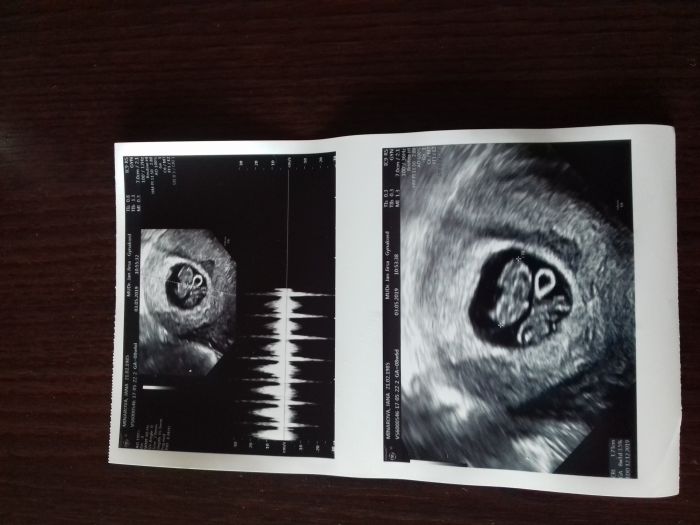

Ahoj holky, tak mam po kontrole a místo jednoho srdicka sem viděla dvě

.Byla sem z toho v soku. A ještě ted to s manželem rozdychavame. Jelikož jsou prcci jednovajecni tak me musí hodně sledovat s musim jezdit do fakultní nemocnice v Olomouci, pojedu tam 16.5.Jinak sem 8+1